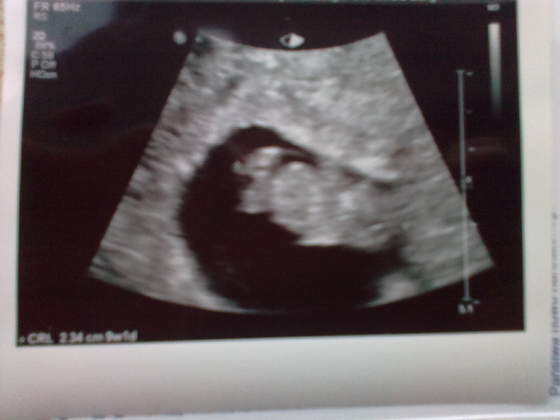

Melduję się po wizycie:) jak widać na załączonym obrazku jest ludzik.Zdjęcie nie jest rewelacyjne bo od przodu i nie za bardzo wiadomo co jest gdzie(przynajmniej ja nie mam wyobraźni) Serduszko super piękne, gin określił moją ciąże na 9 tydzień i 1 dzień termin porodu na 4 października ale mam nadzieję kochane że mnie nie wywalicie z wątku. Amelka była z nami i jak zobaczyła jak fasolka macha nóżkami i rączkami zaczęła krzyczeć miś miś a więc lekarz pogratulował nam misia:-) Kolejne badanie to genetyczne 25 marca.